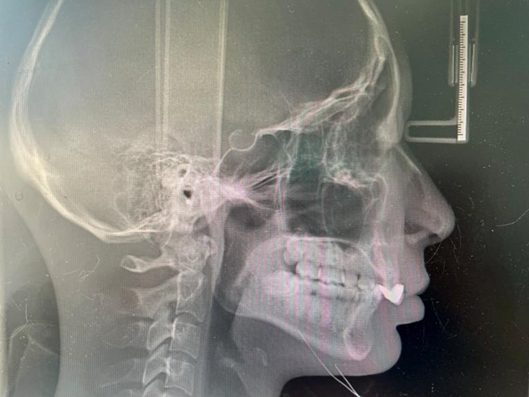

3.头颅侧位片

头颅侧位片主要应用于正畸矫正术前,分析上下颌骨的相对关系、牙齿的位置以及软组织侧貌,从而判断错颌畸形的类型,以便于准确制定正畸或正颌方案,同时也用于做术前术后的对比。